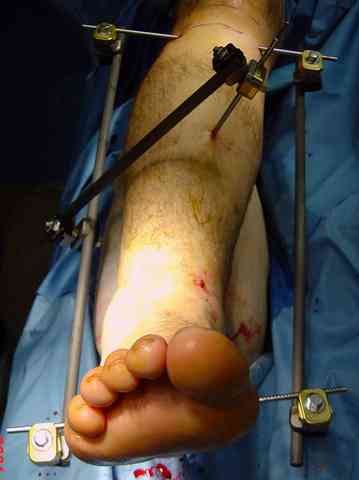

В первые часы после поступления больным экстренно накладывается простой фиксатор из двух поперечно проведенных стержней или сооружается "Delta

Frame" в зависимости от места локализации, и проводится дистракция.

Преимуществ у временного фиксатора много, во первых больной независим, если по другим показаниям нет необходимости находиться в стационаре, то больной может быть выписан домой с возможностью в амбулаторных условиях оценивать состояния мягких ткани на готовность к операции.

Наружным фиксатором обеспечивается длина конечности, предупреждается вторичное сокращение мягких ткани, что является немаловажным фактором для заживления послеоперационных ран. Без фиксатора сокращенные мягкие ткани легко травмируется во время манипуляций, трудно будет провести репозицию, ухудшается местное кровообращение и сохраняется посттравматический отек.

Здесь выставлена пара случаев перелома пилона, оба

случая леченные этапным наружным фиксатором.